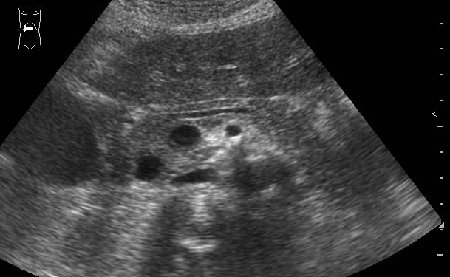

УЗИ панкреас, болевой приступ

Молодая женщина с болями в животе.

- Продольная сонограмма панкреас

Какое заключение можно сделать по этой сонограмме?

Очаговые образования головки ПЖ (кисты?) Рек-но КТ.

Вспоминаем нормальную анатомию!

Жаль нет снимка во взаимоперпендикулярной плоскости.Можно предположить аневризму брюшного отдела аорты.

Холодно. Аневризмы брюшного отдела аорты здесь нет.

По моему это расширенный Вирсунгиев проток,нужно исключать патологию дуоденального сосочка-ФГС